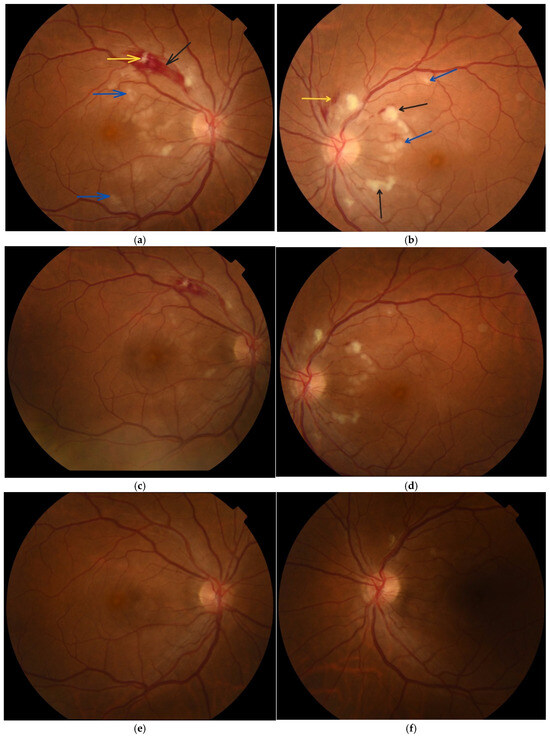

The best-corrected visual acuity (BCVA) upon admission to the ophthalmology clinic was 5/6 in both eyes. Intraocular pressure was 16 mmHg in the right eye and 14 mmHg in the left eye. Biomicroscopic examination of the anterior eye segment showed no pathological changes. Ophthalmoscopic assessment demonstrated the following findings: the optic disc of the right eye was well defined with clear margins, whereas the left optic disc exhibited mildly blurred borders. The macula of the right eye had a clear foveal reflex, which was not present in the left eye. In both eyes, flame-shaped intraretinal haemorrhages were observed along the superior-temporal vascular arcade within the nerve fibre layer, more pronounced in the right eye. In the posterior pole, particularly in the papillomacular region and peripapillary area, there were cotton-wool spots and typical Purtscher fleckens, which were more prominent in the left eye (Figure 1a,b).

Figure 1.

Fundus photography of both eyes: (a,b) at the time of diagnosis of Purtscher-like retinopathy, showing Purtscher fleckens (blue arrow), cotton-wool spots (black arrow), flame-shaped haemorrhages (yellow arrow), involving the posterior pole; (c,d) one week after patient follow-up—changes in the posterior pole are regressing; (e,f) two months after patient follow-up—the haemorrhages, Purtscher fleckens and cotton-wool spots are completely absorbed in the right eye and almost completely in the left. Photographic magnification at 50° 1.84×. Total observation magnification: 10× (50°). Working distance: 39 mm.

Two months following the initial examination, the patient’s visual acuity was 6/6 in both eyes. Haemorrhages, cotton-wool spots and Purtscher fleckens had fully resolved in the right eye and were almost completely resorbed in the left (Figure 1e,f). On OCT, the paramacular hyperreflective areas in the inner retinal layers had progressed to atrophy and thinning in the affected regions. Partial restoration of the ellipsoid zone was observed in the outer retinal layers (Figure 3c,d). Follow-up computerised perimetry demonstrated a reduction in areas of decreased light sensitivity (Figure 6c,d).